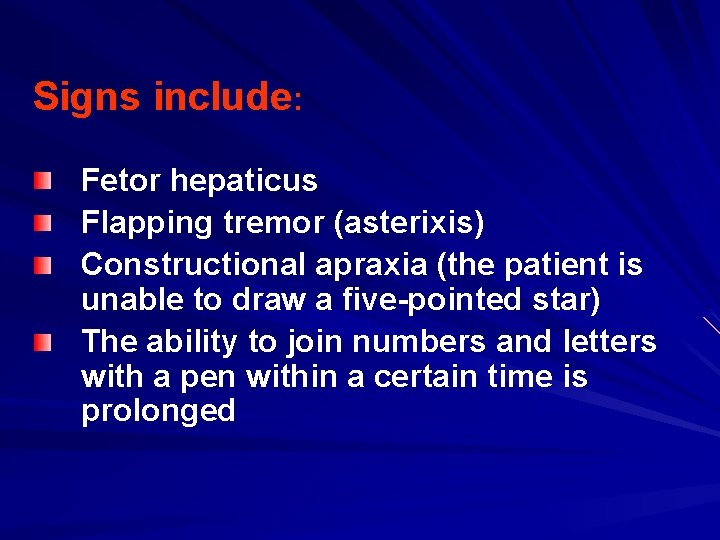

Signs include: Fetor hepaticus Flapping tremor (asterixis) Constructional apraxia (the patient is unable to draw a five-pointed star) The ability to join numbers and letters with a pen within a certain time is prolonged